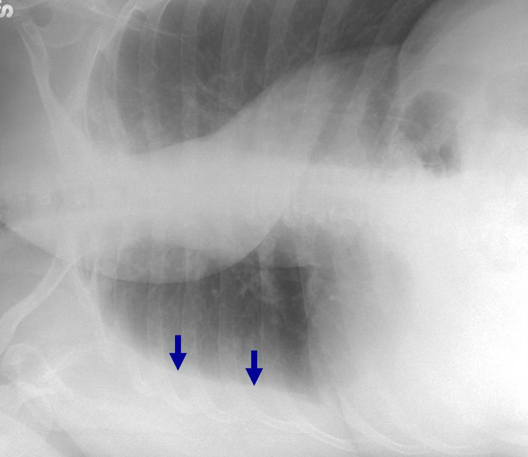

What is blue arrow pointing to?

Blebs (pockets of air) in COPD pt